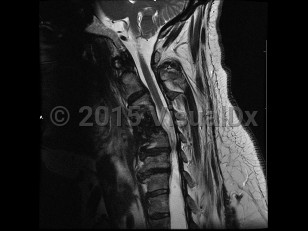

Syringomyelia is a cavity or syrinx within the spinal cord that can expand over time. Although the underlying pathophysiology is incompletely understood, syringomyelia is thought to form because of abnormal flow of the cerebrospinal fluid (CSF), and this dysfunctional pressure gradient causes fluid to build up in the spinal cord. Acquired syringomyelia may result from hydrocephalus, infection, inflammation, trauma or spinal cord injury, intramedullary or extramedullary tumors, spinal canal stenosis, vascular malformations, or bony abnormalities. Overall, the prevalence of syringomyelia varies worldwide, ranging from approximately 2-8 per 100 000. Age of onset varies by cause.

Symptoms depend on the location of the lesion; most occur in the cervical region, between C2 and T9. In some cases, patients are asymptomatic, and syringomyelia is an incidental finding on imaging. Cervical syringomyelia typically manifests as early impairment of temperature and pain sensation in a cape-like distribution over the back and arms, and weakness that is greater in the bilateral upper extremities compared with the bilateral lower extremities. There may also be chronic pain. Neurologic examination may be notable for loss of reflexes, light touch, vibration, and joint position sense; weakness and atrophy of the hands; and lower extremity spasticity and hyperreflexia. Bladder, bowel, and erectile dysfunction can occur as late manifestations.